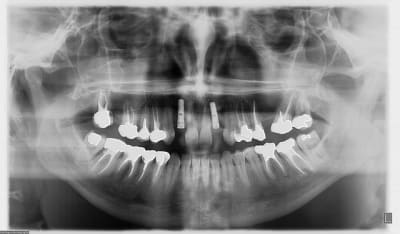

jeune homme,

18 ans,

agénésie de 12,

extraction de 52 depuis 2 ans et remplacement par un mainteneur d'espace, vient consulter pour un implant...

j'adore ce genre de cas, c'est un vrai défi esthétique où on a pas le droit à l'erreur.

je pense qu'une greffe osseuse serait peut être nécessaire pour la concavité. Toutefois, je devrais pouvoir m'en sortir en dilatant la crête osseuse vestibulaire pendant la pose de l'implant.